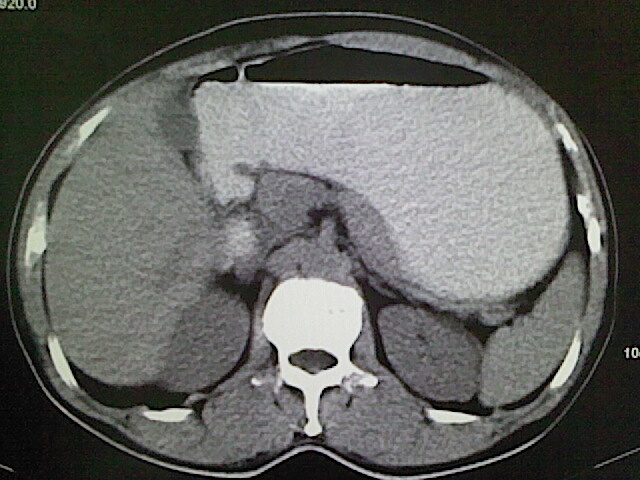

标题: CT18630:男,54岁,乙肝,大家看怎么样? [打印本页]

男,54岁,乙肝,大家看怎么样?

未见明显异常!(另:患者有乙肝病史,应定期做彩超检查!)

肝脏的要有增强敢说话

未见明确异常;建议必要时行ct增强扫描检查。